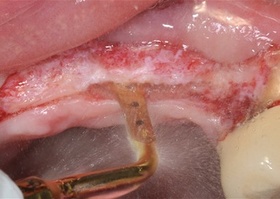

Removal of teeth and roots, alveolar plastics, NTR, together with implantation No. 4

15 january 2018, Maria Alexandrovna Nosova, Saint-Petersburg

Removal of the 11th and 21st teeth. Single-stage implantation, plastic of the vestibular defect Lyoplast Mix-MAX and plastic of the gum with TMO (dura mater) of the 21st tooth